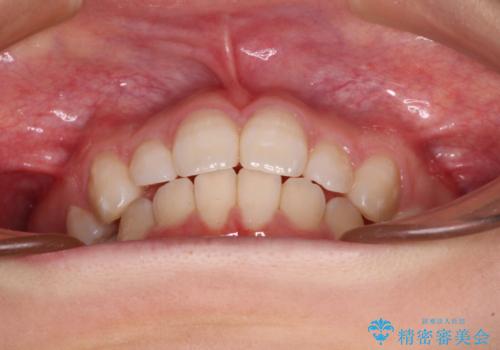

- 下顎前歯を中心に、以前行った矯正治療の後戻りが気になるとのことで来院された患者様です。

後戻りは軽度であったため、インビザライン・ライトにて治療を行うこととしました。

治療途中で出産をされたため、通院が困難となりましたが、インビザライン・ライトでの治療可能期限である2年以内に無事に治療を終えることができました。